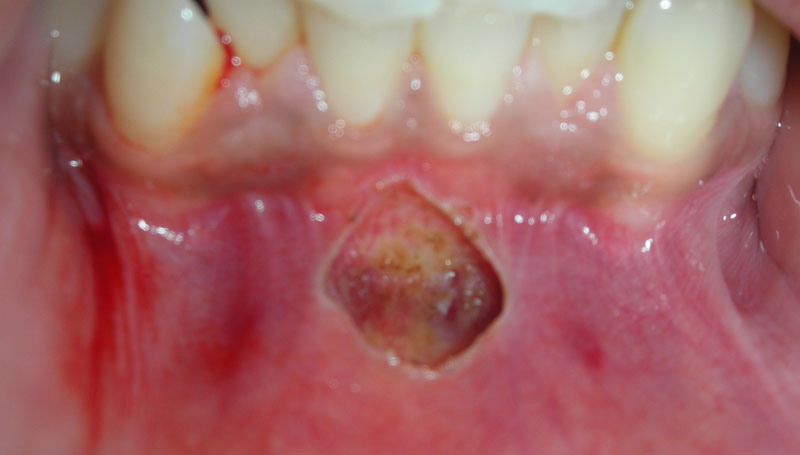

Fibroma

Before